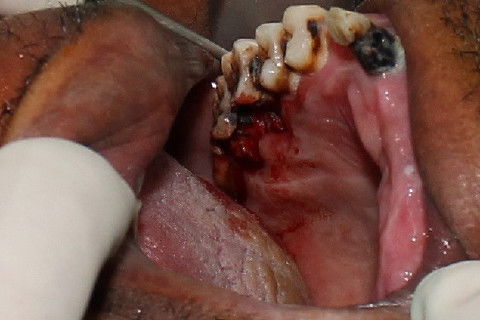

Luxação e avulsão do elemento 17. Fóceps 18R

Luxação e avulsão do elemento 16. Fóceps 18R

Elemento 16 sendo avulsionado.

Visão dos alvéolos vasios e do dente 18 indicado para extração, visto que apresentava processo carioso e não possuia um antagonista para ocluir.